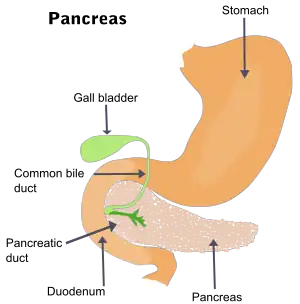

Le cancer du pancréas est un cancer de la glande pancréatique (située derrière l’estomac et qui sécrète les enzymes digestives).

Il en existe deux catégories, selon la partie du pancréas touchée. Cette glande est double, avec :

- une partie exocrine qui sécrète les enzymes digestives ;

- une partie endocrine dont le rôle est hormonal (plusieurs hormones importantes dont l'insuline y sont synthétisées et distribuées).

- si le cancer est situé sur la tête du pancréas (60-70 % des cas[7]), il crée un obstacle des voies biliaires responsable d'une dilatation rapide de la vésicule biliaire, d’un ictère (par rétention biliaire)[3] et d’un prurit (démangeaison) causé par l'ictère[28] ;

- si le cancer concerne la queue ou le corps du pancréas (20 à 25 % des cas[7]), le tableau clinique est dominé par des douleurs épigastriques transfixiantes (irradiantes vers les lombes[3]), accompagnées d'une masse épigastrique.